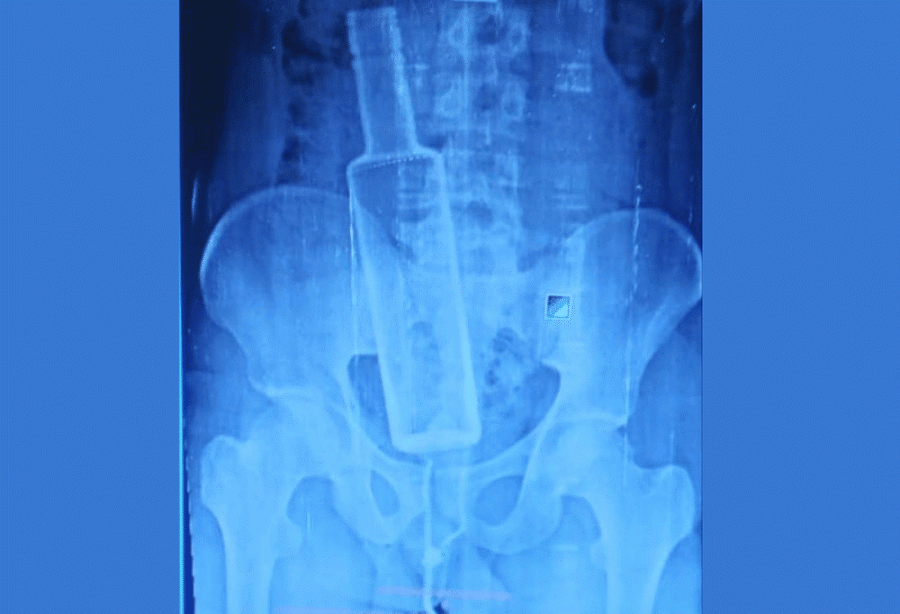

The shocking incident came to light after the victim, Nurshad Mansuri, visited a hospital after complaining of persistent abdominal pain. An X-Ray of the victim’s stomach revealed the bottle, stuck inside his body.

The doctors and medical staff were surprised after reports revealed an entire bottle inside the patient’s body.

Dr Abhishek Adhikari, who attended Mansuri at the Chandrapur Hospital, referred the patient to Bharatpur immediately after the X-Ray revealed the foreign object, stuck in the rectum.

“We were shocked to find an entire glass bottle in his body,” Adhikari said. “We referred him to a hospital with better facilities, fearing serious problems that could arise if proper care was delayed.”